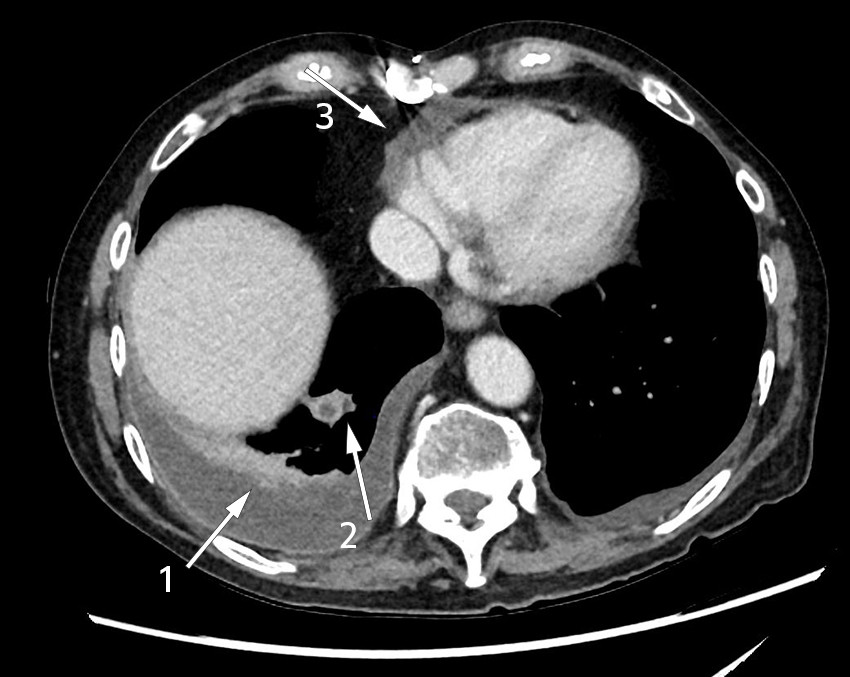

Six weeks after starting treatment for postcardiotomy syndrome and six months after the aortic valve surgery, the patient was admitted for the ninth time as an emergency to the department of medicine. In addition to the dyspnoea, swelling of the legs and palpitations seen in the previous admissions, he had chills and pain in the right calf and knee. He was found to be in a diminished general condition on clinical examination. He was afebrile and had normal blood pressure of 112/80 mmHg, regular pulse of 104 bpm and oxygen saturation of 95 % without oxygen administration. There were decreased bibasilar breath sounds as in pleural effusion, friction sound over the precordium, slight swelling of the right knee and an unremarkable scar following sternotomy. Unlike in previous admissions, the patient's inflammatory markers were significantly elevated with leukocytes 18.2 ×109/L (3.5–10.0 ×109), CRP 224 mg/L (< 4.0) and ESR 107 mm (< 12). Chest CT showed right-sided pleural effusion with pleural reaction, which was regarded as inflammation or infection, as well as a smaller lesion suspected to be an abscess in the right lung (Figure 1). Based on the clinical presentation and radiological suspicion of pneumonia with possible empyema, empiric treatment was initiated with cefotaxime 2 g three times daily for coverage of nosocomial aetiology. The results of bacterial culture and PCR testing of nasopharyngeal specimens for respiratory pathogens, including SARS-CoV-2, were negative.

Inoculation of Nocardia spp. during open heart surgery has not been described in the literature. The absence of local infection in the surgical site both clinically and on PET and CT scans also suggests that this was not the case in our patient. Contrast enhancement in the pleura, pleural effusion and a lesion suspected to be an abscess in the lung (Figure 1) could be due to both postcardiotomy syndrome and nocardiosis, and it was challenging to distinguish between inflammation and infection. Although we never managed to detect the microbe in pleural effusion or the respiratory tract, we assume that the lower respiratory tract was the primary focus, with further haematogenous spread to the brain and muscles of the lower extremities.